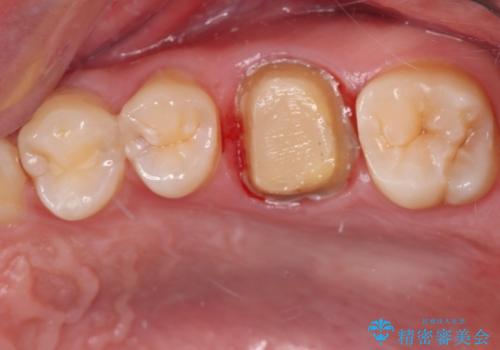

右下の銀の詰め物は、外してむし歯を除去した後、セラミックインレーにて修復することとしました。

左上の銀歯は、銀歯の下に金属の土台が入っているため、その土台を除去し、ファイバーコアにやり替えて、オールセラミッククラウンにて補綴することとしました。